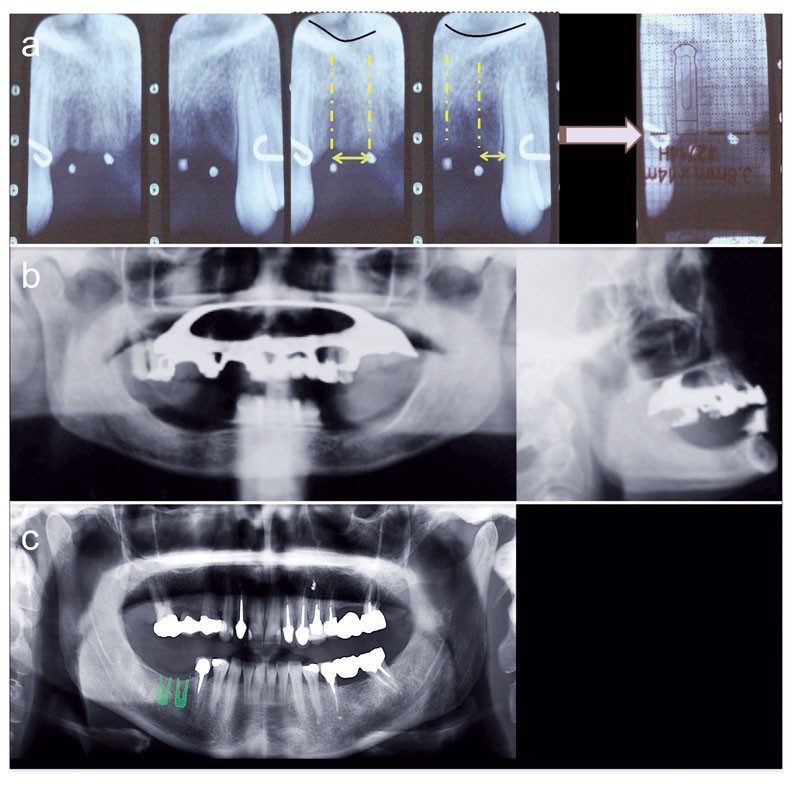

L’imagerie en implantologie orale est l’un des éléments essentiels de la démarche diagnostique, de la sélection des patients et enfin de la planification chirurgicale et prothétique. Même si l’imagerie sectionnelle n’est jamais réalisée en première intention, le passage d’examens bidimensionnels à des examens tridimensionnels a bouleversé les protocoles de traitement. L’exploration de la troisième dimension axiale avec des techniques fiables et peu irradiantes optimise la prise de décision et la gestion des risques. Désormais, la Tomographie Volumique à Faisceau Conique (TVFC) est considérée comme une technique de référence en imagerie sectionnelle et supplante le scanner. Leur couplage à des logiciels de planification autorise une navigation rapide et dynamique au cœur de l’anatomie du patient ainsi qu’une simulation de toutes les étapes en amont de la chirurgie. La superposition d’un calque et d’une planche de scanner devient totalement obsolète.

L’imagerie en implantologie orale est un élément essentiel de la démarche diagnostique, de la sélection des patients et de la planification chirurgico-prothétique. Le passage des examens bidimensionnels (2D) – aux limites évidentes – à des examens tridimensionnels (3D), tels que la tomodensitométrie (TDM) a modifié la prise en charge des patients en implantologie. Le début des années 2000 a connu l’arrivée d’une innovation technologique majeure : la Tomographie Volumique à Faisceau Conique (TVFC) qui permet une exploration limitée aux structures maxillo-mandibulaires et dento-alvéolaires au prix d’une irradiation plus faible que la TDM. En 2002, dans un souci d’harmonisation, l’European Association for Osseointegration (EAO), jette les bases de l’imagerie diagnostique en implantologie, en proposant un référentiel pour l’usage raisonné de l’imagerie sectionnelle. Depuis, la mise en application de la directive Euratom 97/43 (1), la Haute Autorité de Santé (HAS) en 2009 et l’EAO en 2012, consacrent la TVFC comme la technique de référence en imagerie sectionnelle dento-maxillaire, devant le scanner dentaire (2). Les applications chirurgicales et prothétiques des examens tridimensionnels ainsi que l’avènement de l’implantologie assistée par ordinateur (IAO) ont fait évoluer les protocoles implantaires. Aujourd’hui, l’adaptation de la chirurgie aux impératifs prothétiques est plus que jamais une réalité, grâce à l’optimisation en pré et en peropératoire, de la position spatiale de l’implant en fonction des critères esthétiques, fonctionnels et biomécaniques.